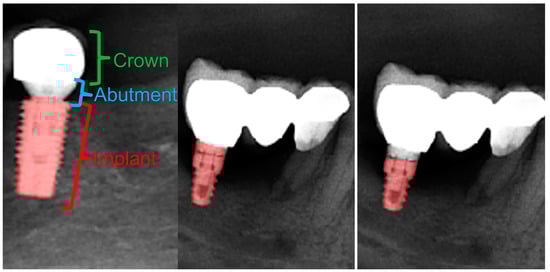

Figure 11.

Crown–abutment and implant parts of a dental implant with a crown (left). Manual segmentation of the dental implant (middle) and automatic segmentation of the dental implant (right). Note that the abutment part and the superior portion of the implant were not segmented by our model in this case.

Although the DSC for dental implant segmentation was 0.94 in our study, after checking the output data it was seen that the implant abutments were segmented as dental implants or crowns (Figure 11).

In a systematic review conducted by Revilla-Leon et al., it was reported that the automatic segmentation of dental implants by AI models was between 93.8% and 98% in the literature [93]. Similar to the literature, our model was successful, with a DSC value of 0.94. Due to both their external structures with grooves and metallic opacities, dental implants were not mis-segmented as any anatomical structures or restorations, and the automatic segmentation had an almost perfect DSC. When the reasons for the relatively lower DSC in implant segmentation were examined, it was seen that our model randomly segmented the implant abutment in some OPGs and not in others; therefore, it is fair to state that, in further studies, segmentations of dental implants, abutments, and the crowns on implants via three separate labels might increase the DSC, as mis-segmentation between the abutment and the implant will not be present.